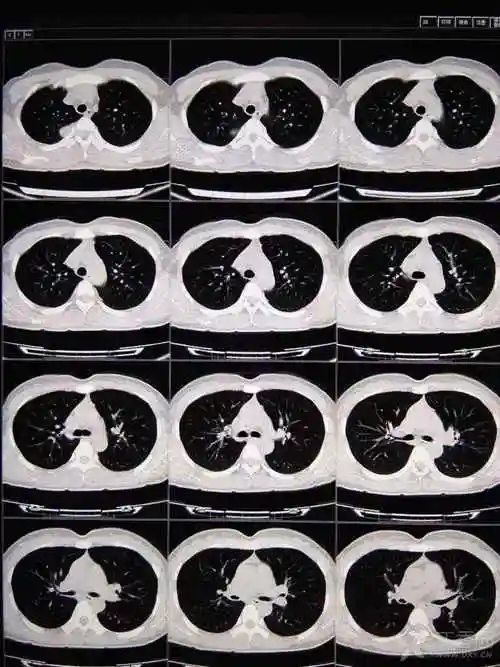

典型病例发一个,"哑铃征" ,不用鉴别诊断 - 丁香园论坛